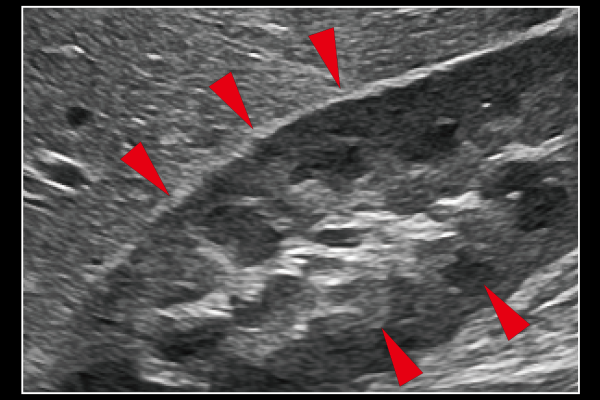

周囲組織の質感や表現を保ちながら、血管壁などの組織構造を明瞭に描出します。進化したエッジ強調処理技術によって、構造物を効果的に抽出することが可能です。

Carving Imaging ON